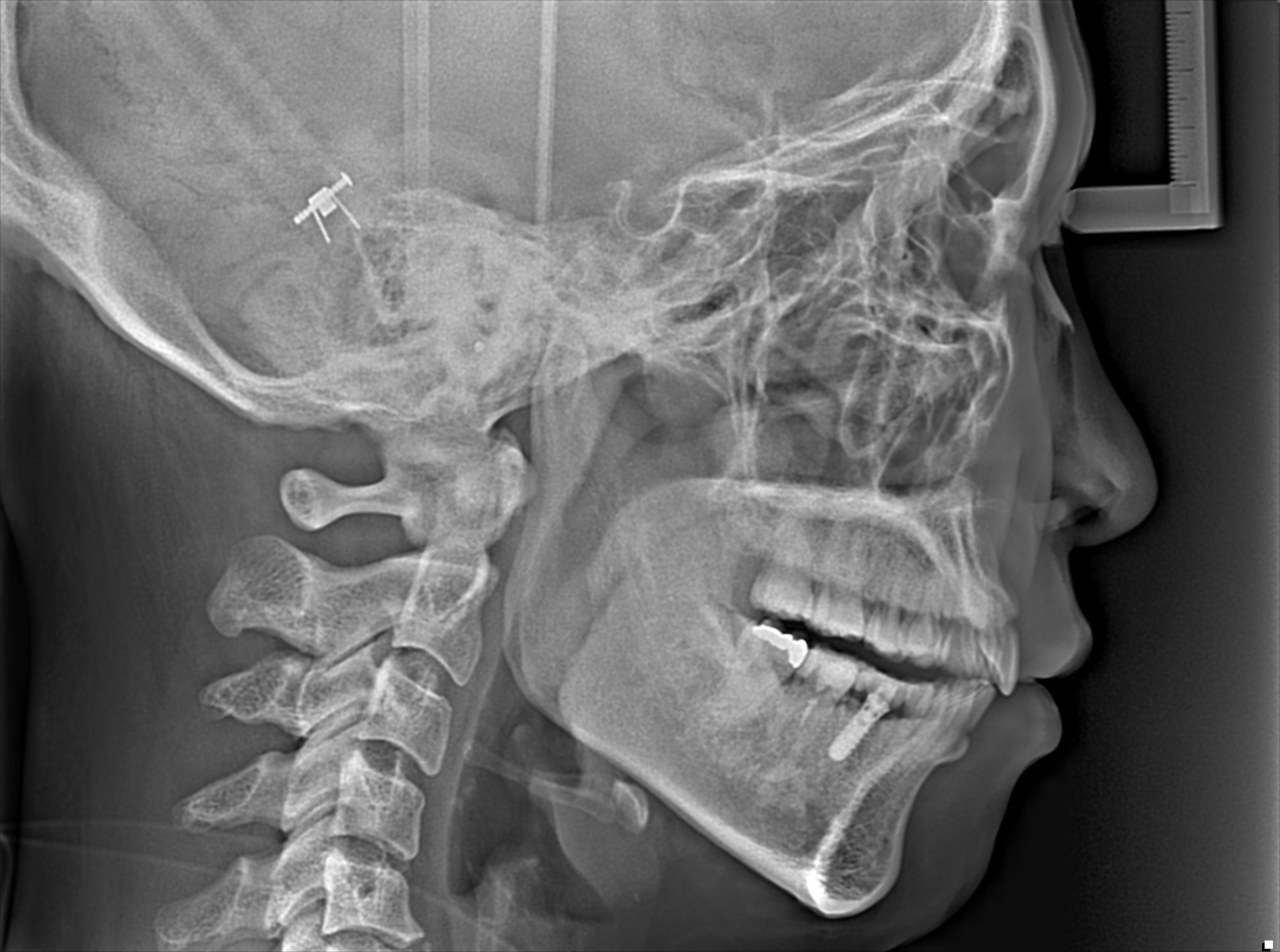

②セファロ

側方

セファロは矯正歯科特有のレントゲンです

正式には『頭部X線規格写真』といいます

撮影する条件が決まっており

名前にあるように『規格』化されています

そのため事前にレントゲン上で角度計測などを行い

歯列矯正後にその角度などを比較することもできます

特に側方のセファロを利用すると

横顔の改善(前歯の前突、口元の突出など)

をデジタルシミュレーションすることも可能です